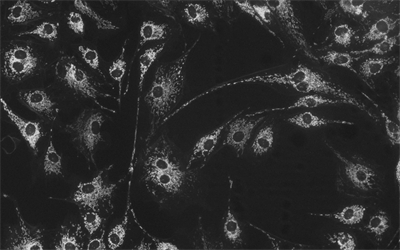

MHS700-MC(黑白)相機(jī)采用Sony Exmor CMOS芯片,針對傳感器固有的熱噪聲,專門設(shè)計了高效制冷模塊使得相機(jī)傳感器的工作溫度比環(huán)境溫度低達(dá)-40度,大大降低了圖像噪聲,保證了圖像質(zhì)量的獲取。

分辨率橫跨710萬,實時8/12位切換,任意ROI尺寸,Ultra-FineTM顏色引擎確保顏色精準(zhǔn)再現(xiàn),快速地完成對相機(jī)的各種設(shè)置,曝光超速抓拍,實現(xiàn)完美顏色再現(xiàn)能力。

相機(jī)可用于弱光或熒光圖像的拍攝與分析,主要應(yīng)用于以下領(lǐng)域顯微拍攝:

• 活體細(xì)胞成像,細(xì)胞或組織病理學(xué)檢測,細(xì)胞學(xué);

• 微光熒光成像,GFP 或 RFP 分析,熒光原位雜交(FISH);

• 熒光共振能量轉(zhuǎn)移顯微鏡,全內(nèi)反射熒光顯微鏡,實時共聚焦顯微鏡,失效性分析,天體照相。